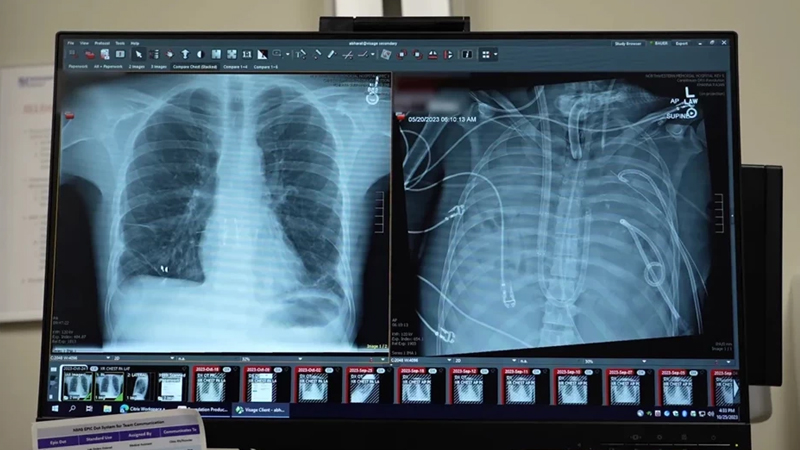

Hər şey sağlam bir kişinin Influenza B virusuna yoluxması ilə başlayıb. Əvvəlcə adi qrip kimi görünən vəziyyət qısa müddətdə kəskin tənəffüs çatışmazlığına çevrilib və xəstəxanaya çatdırıldıqda vəziyyəti artıq kritik həddə çatmışdı. Antibiotiklər və ənənəvi oksigen müalicələri ağciyərlərdəki dağıntını dayandırmağa kifayət etməyib. Ağciyərlər o qədər ağır zədələnib ki, həm ürək, həm də böyrəklər fəaliyyətini itirməyə başlayıb. Əməliyyata rəhbərlik edən professor Ankit Bharat bildirir ki, xəstə xəstəxanaya çatdığı an ürəyi dayanıb və ağciyər toxuması geri dönməz şəkildə sıradan çıxıb. Bu mərhələdə klassik üsullar yetərsiz qaldığı üçün tibb komandası radikal qərar verərək infeksiya ocağına çevrilmiş ağciyərləri tamamilə çıxarmağa və xəstəni süni bir sistemlə həyatda saxlamağa cəhd edib.

Ağciyərlərin bədəndən çıxarılması infeksiyanı nəzarət altına almaq üçün yeganə yol idi, lakin bu, çox böyük texniki problemi də ortaya çıxarıb. Ürək və ağciyərlər bir-biri ilə sıx bağlı olduğundan, ağciyərlər olmadan qanın oksigenlə təmin edilməsi və zəifləyən ürək ritminin qorunması demək olar ki, mümkünsüz sayılırdı. Mütəxəssislər mövcud texnologiyaları daha da təkmilləşdirərək qanın bədən xaricində oksigenləşdirilməsini təmin edən və ürək üzərindəki təzyiqi tarazlayan xüsusi sistem qurublar. Bu süni mexanizm iki gün ərzində xəstənin qanındakı karbon qazını təmizləyib oksigen təmin edərək digər orqanların bərpasına vaxt qazandırıb.